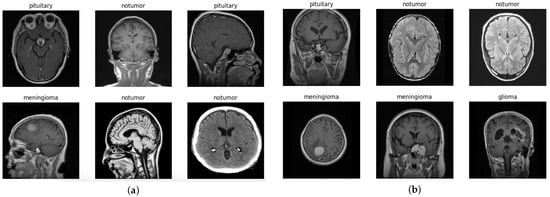

The images are two-dimensional, grayscale, and represent axial slices of MRI scans (Figure 3). The image resolution is standardized to 512 × 512 pixels, which facilitates preprocessing operations.

Figure 3.

Dataset images. (a) Examples of training dataset images. (b) Examples of testing dataset images.

This organization allows the development and evaluation of models capable not only of detecting the presence of tumors but also of distinguishing between glioma, meningioma, notumor, and pituitary classes. Figure 4 shows the number of images for each training and testing class in the dataset. Despite slight variations among classes, the dataset can be considered reasonably balanced, which benefits classification model performance and reduces the risk of bias towards any dominant class.